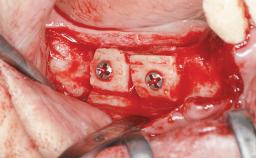

Horizontal Augmentation with Iliac Bone Grafts in the Treatment of Non-Syndromic Oligodontia

A 20-year-old woman was referred for implant therapy in 2004. Her medical history revealed no significant findings, and neither did she smoke nor take any medications. An extraoral examination revealed no abnormalities of the skin, hair or nails. The intraoral examination revealed only 11 permanent teeth clinically. These were normal in shape, size, and color. In addition, eight retained deciduous teeth (53, 62, 63, 71, 72, 73, 81, 82) were present. No abnormalities were detected during the general examination. The family history revealed that the patient’s father and two sisters were on record with similar conditions. The clinical examination revealed a thick gingival biotype. No recession of the attached gingiva was noted, but the retained deciduous teeth were mobile and unsightly. As a syndrome had not been diagnosed, the case was categorized as non-syndromic oligodontia.

Bone Augmentation Horizontal|Staged

Augmentation Materials Autogenous chips|Autogenous block(s)|Membrane

Bone Volume Deficient horizontally, requiring prior grafting